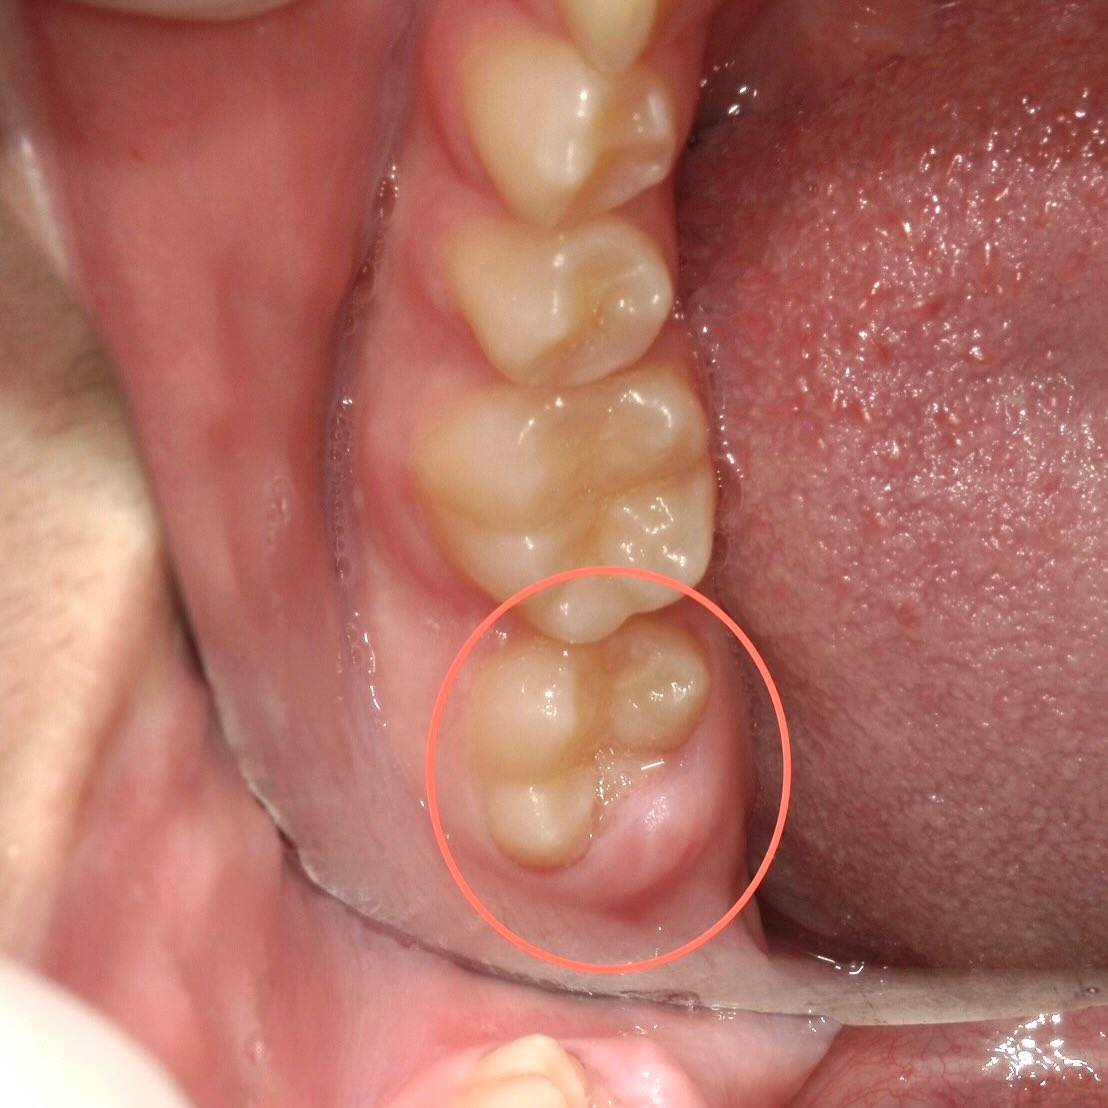

歯が生えてきてから物を噛むと痛い!と来院した患者さんの写真です📸

12歳の患者さんなのですが、左下の7番目の奥歯がついこの間生えてきたとの事です。

それに伴い物を食べると歯茎が痛むようになった、と言っていました🧐

この症状、生え変わりの際によくある所見で、「萌出性歯肉炎」といいます✍️

歯が生えてくる際、歯の一部がまだ歯ぐきに覆われている段階で起こりやすいです。